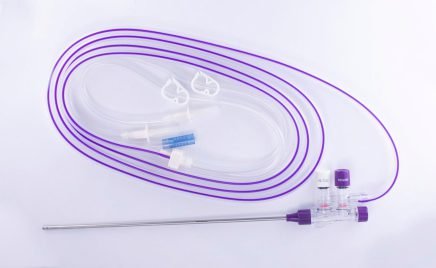

Essential Laparoscopic Suction / Irrigation System

Elite Laparoscopic Suction / Irrigation Sets